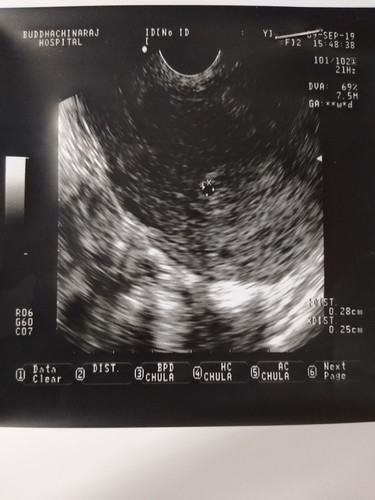

รุ้ตัวว่าท้องตอน4weed แล้วไปอยู่ๆผ่านมาสักอาทิตย์มีเลือดออกเลยได้ซาวครั้ง รูปแรก และหมอให้ยากลับบ้านกินยานอน พอตอนเย็นมีปวดท้องและมีเหมือนก้อนเลือดออกมาด้วย เลยกลับไปหาหมออีก หมอก็ซาวดูเห็นหัวใจน้องยังเต้นอยู่และให้ยาหยุดเลือดมาทาน ให้นอนพัก เลือดออกอยู่ประมาณ 1 สัปดาห์ค่ะกะหยุดตอนนั้นน่าจะได้ 6 weed และอาการเจ็บนมหายไปแต่อาการอื่นยังอยู่ เลยสงสัยว่าน้องยังอยู่รึป่าวผ่านมาประมา1สัปดาร์ 7 weed เลยไปคลีนิคเพื่อดูน้องว่าอยู่หรือป่าวเพราะรอหมอนัดอีกไกลเหลือเกิน รูปสอง ไปนั่งตรวจไม่ถึงสิบนาที หมอคลีนิคบอกน้องไม่อยู่แล้ว งื้ออ ช่วยดูหน่อยค่ะว่าน้องยังอยู่หรือป่าว ขอบคุณค่ะ